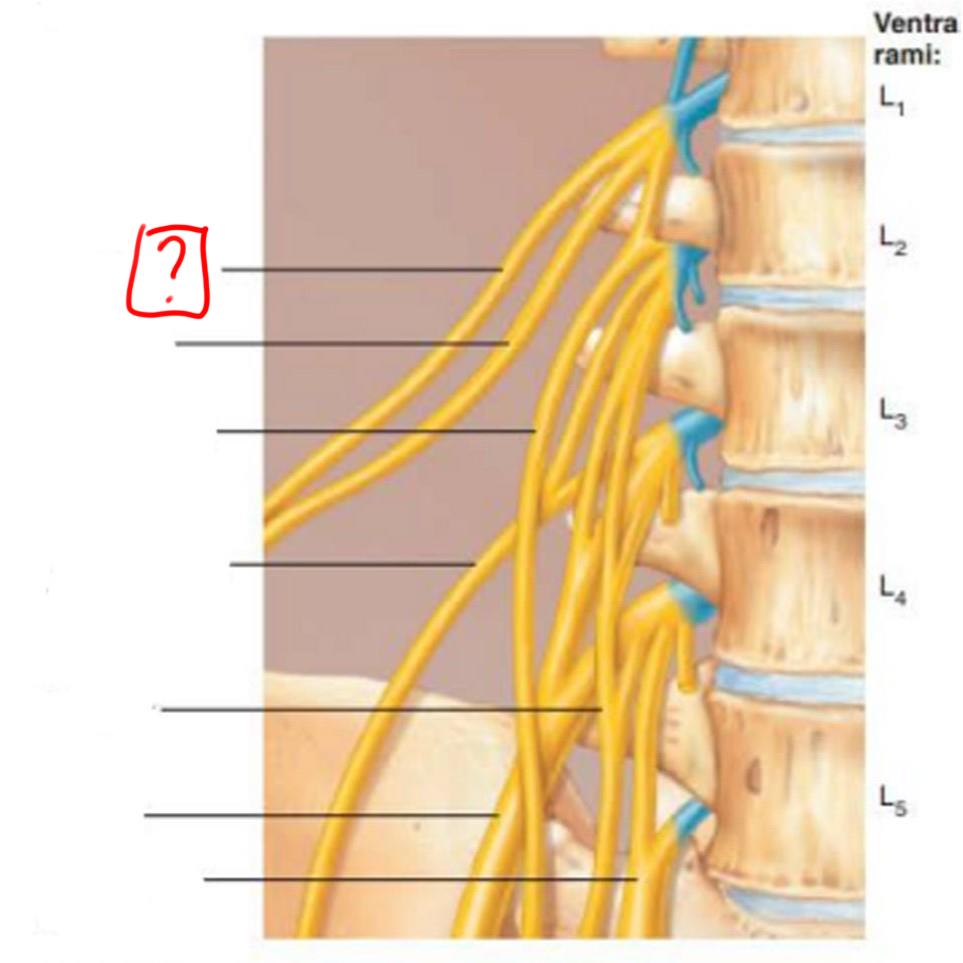

lumbar plexus

L1-L4

major nerves: ilioinguinal, obturator, femoral, genitofemoral

iliohypogastric

ilioinguinal

genitofemoral

lateral femoral cutaneous

obturator

femoral

lumbosacral trunk